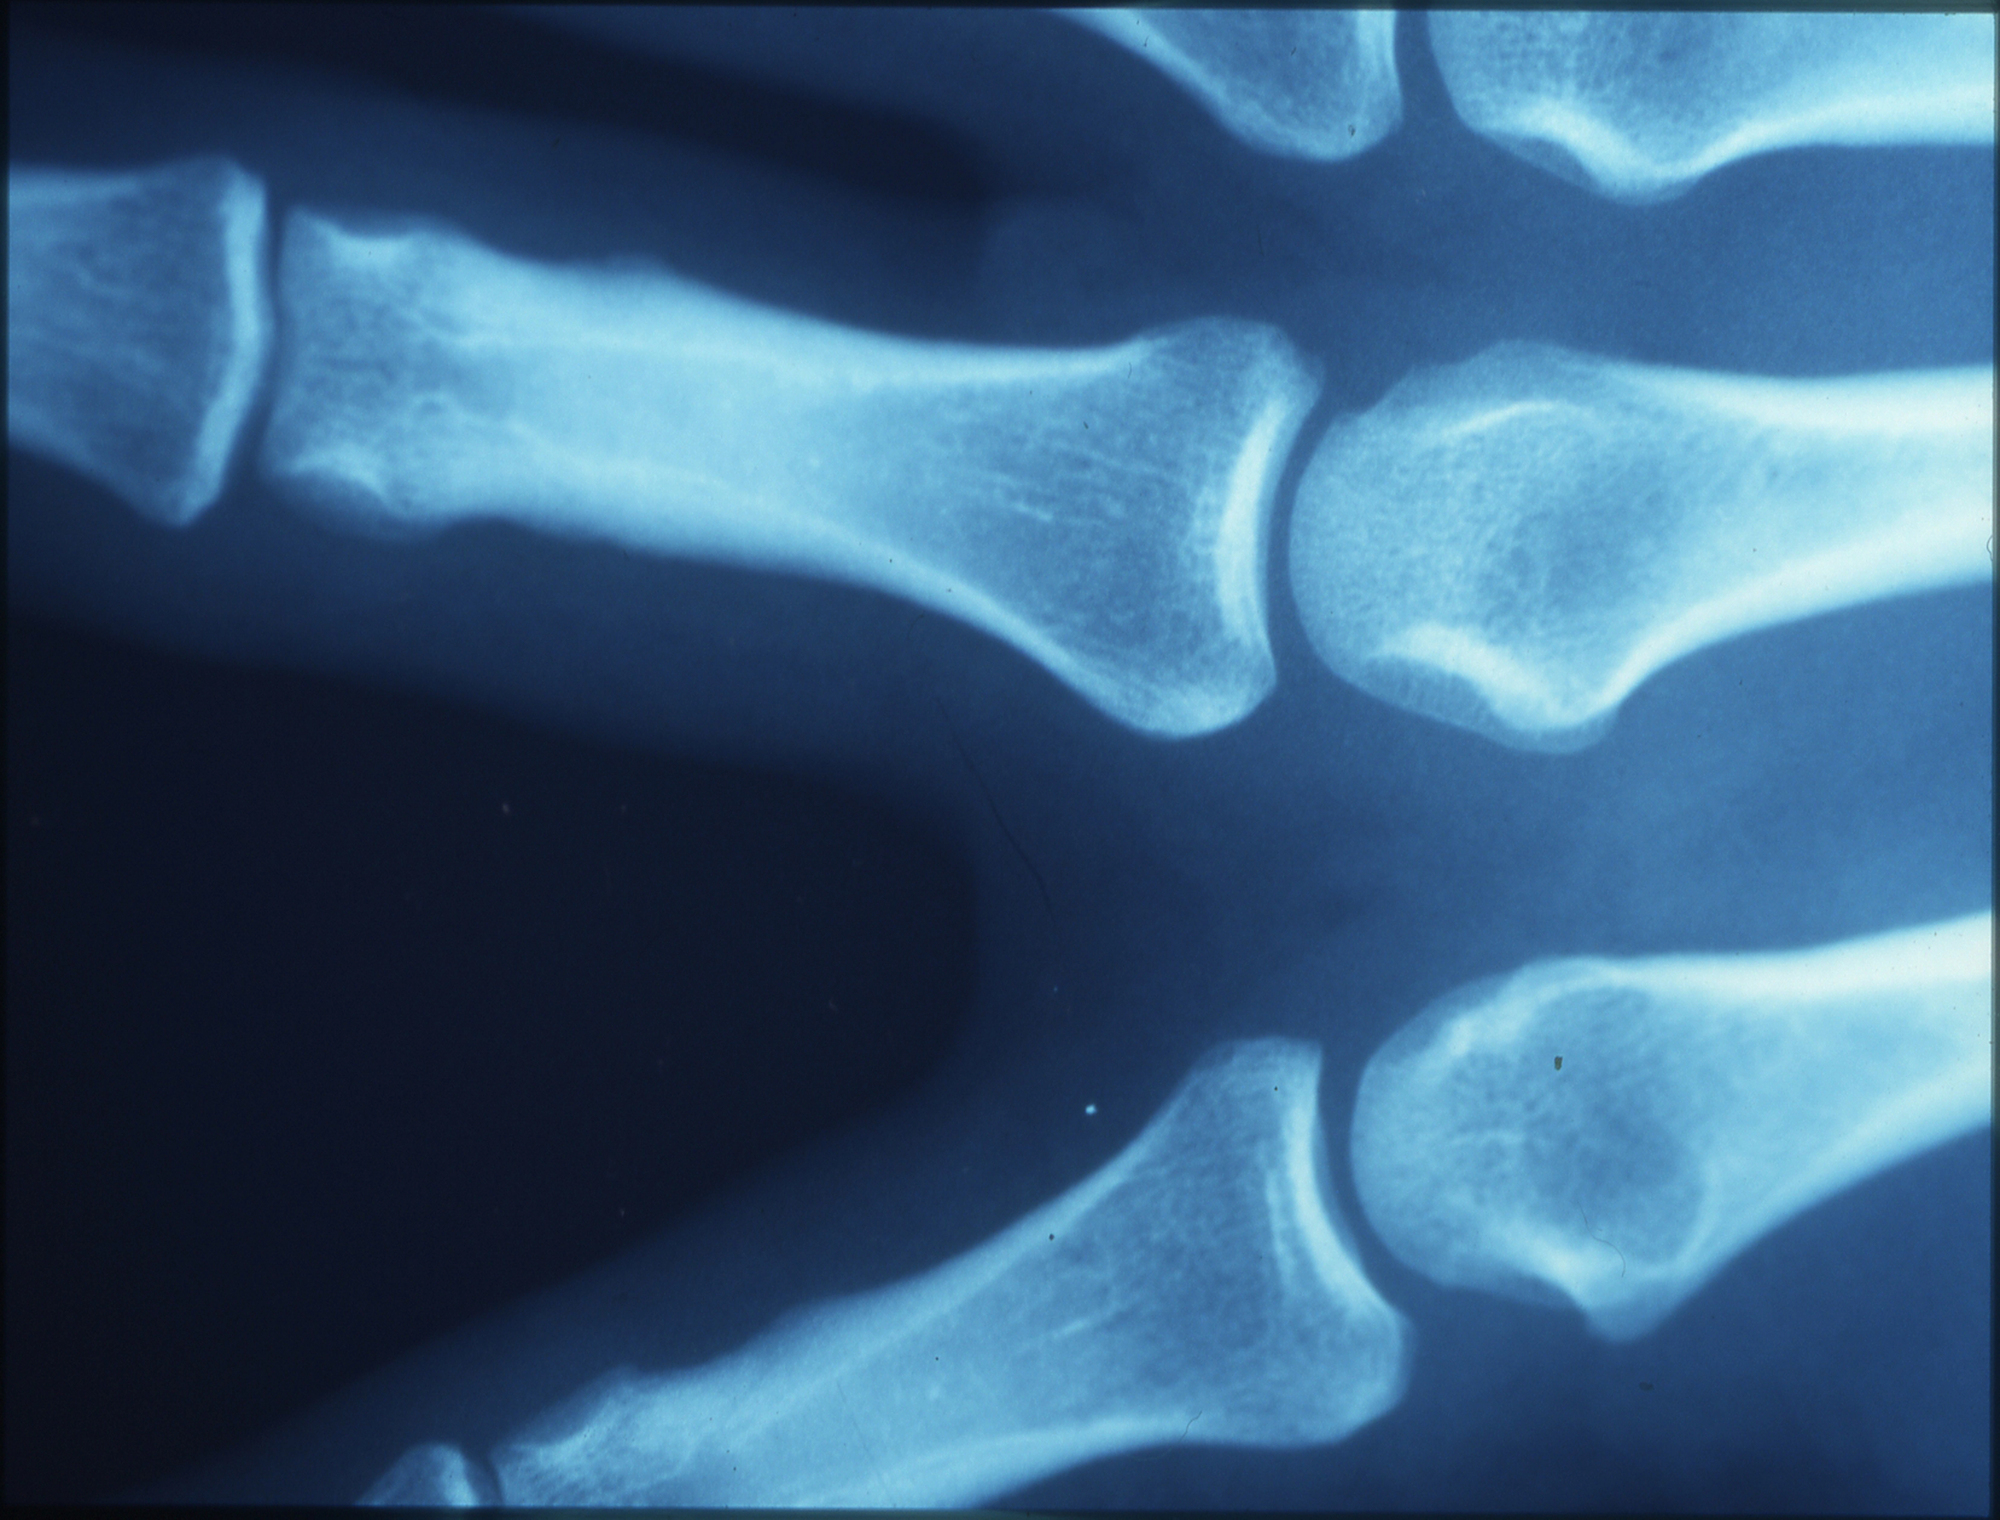

One of the most common contributors to long-term joint discomfort is osteoarthritis, a degenerative joint condition characterized by gradual cartilage breakdown and changes in the surrounding joint environment. As cartilage thins and joint mechanics shift, everyday activities may become increasingly uncomfortable.

Inflammation plays a central role in how joint pain develops and persists. While short-term inflammation is part of the body’s natural healing response, chronic inflammation can contribute to ongoing tissue irritation, cartilage wear, and heightened pain sensitivity.

In joints, prolonged inflammatory signaling may alter joint fluid composition, impair normal tissue repair, and accelerate degenerative changes. Because of this, many modern approaches to joint health focus on addressing inflammation rather than solely masking pain symptoms.